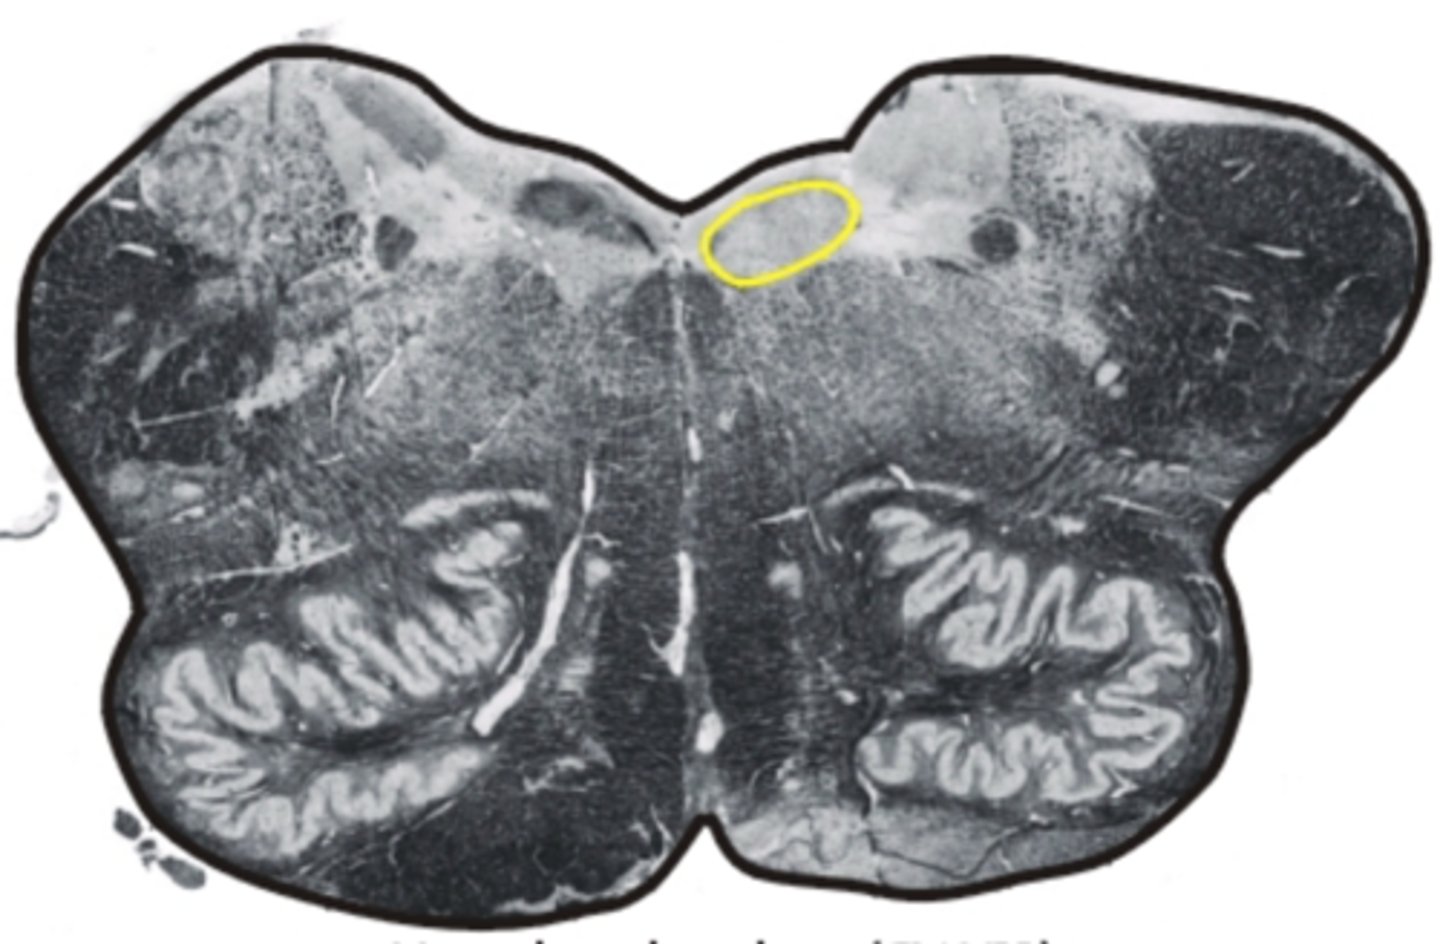

pons

center structure of the brain stem, located between the midbrain and the medulla oblongata

pontine nuclei

serves as relay striations between cerebral cortex & cerebellum in regards to motor coordination